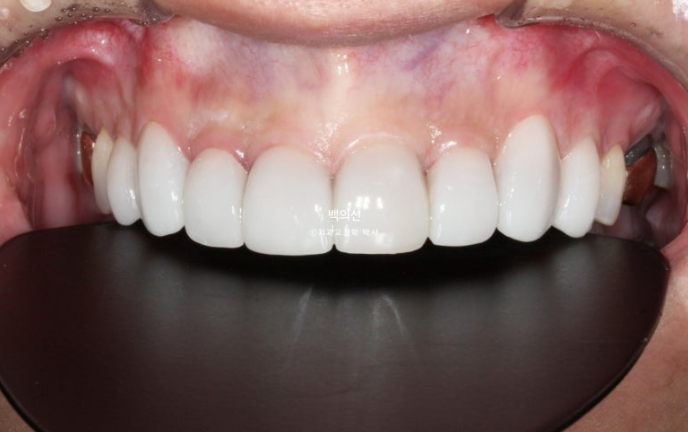

This is what the Gelami looks like on the 8 upper front teeth.

This is what the Gelami looks like on the 8 lower front teeth.

This is an occlusal surface photo that gives an idea of the thickness of Gelami.